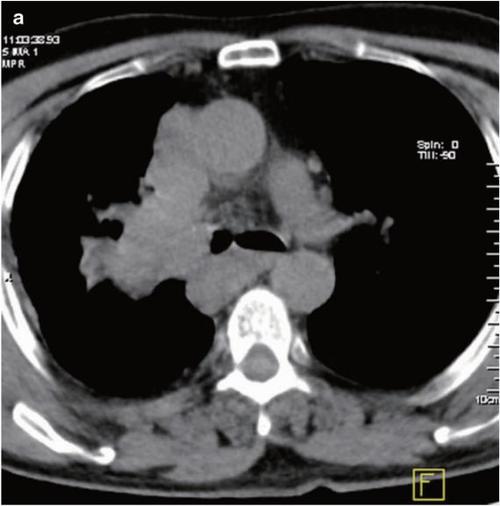

(3)压迫上腔静脉引起面部,颈部,上肢和上胸部静脉怒张,皮下组织水肿

这名患者中,肺癌引起了什么并发症?丨看图识癌

病例小细胞肺癌1例ct影像表现